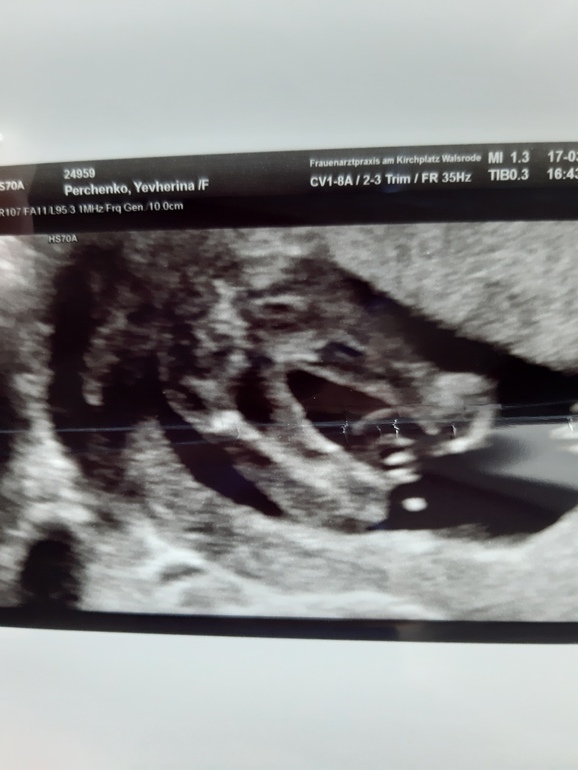

Мальчик или девочка УЗИ 16 недель

Врач сказала скорее всего девочка но не точно. Смущает первое фото лично меня. У моего мужа от первой жены два сына и у нас с ним сын. Хотим очень девочку но как то уже не верится

На первом фото вообще ничего не разобрать, а второе ножки попа и между ножек нет писюна тоже считаю что девочка у вас)

На первом фото для писюня слишком мал. Кость скорее всего. И яйки бы плавали. Девочка у вас наверное💐👏👏👏

похоже на бедренную кость

Девочка, на втором фото у мальчика явно уже должно было быть всё видно. Не знаю, что за сомнения у врача. У моих в 15-16 недель уже было прям очевидно видно пол и нам с мужем показывали, либо писюн , либо половые губы и там было ну вообще без сомнений.

На первом фото, может, пуповина так легла просто..